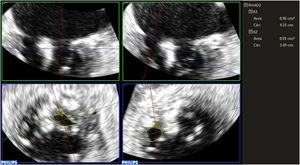

METHODSA prospective registry was created, including 167 consecutive patients who underwent percutaneous edge-to-edge mitral valve repair at our center from October 2010 to May 2023. Transesophageal echocardiography for the procedure was performed using a Philips Epic 7 system and X7-2t probe (Philips Medical Systems, United States). All measurements were carried out in accordance with clinical practice guidelines.1,4,8 Continuous Doppler with transesophageal echocardiography was used in the catheterization laboratory immediately before starting the procedure and after releasing the last clip to evaluate the mean transmitral gradient and MVA using the PHT method.9 The Doppler beam was positioned at the center of the largest orifice to obtain a high-quality Doppler spectrum. For both the gradient and PHT measurements, the average of 3 beats was used, while 5 beats were averaged in patients with atrial fibrillation. If transmitral flow showed 3 slopes, an initial steep slope followed by a more gradual one, the mid-diastolic segment was used for PHT calculations, as recommended in clinical practice guidelines.1,4,8 In addition, 3D zoom acquisitions of the mitral valve were performed to measure MVA by 3D planimetry using Philips Medical Systems 3D quantification software (3DQ) (figure 1). The mitral valve is shown using 3 orthogonally oriented planes. To avoid overestimating the MVA, the plane used for measurement is oriented perpendicular to the valve leaflets.10,11 After clip placement, the 3D area of each orifice was measured separately, as the orifices typically have different orientations in space (figure 1). The total MVA was then calculated by summing the areas of both orifices. The study was approved by the hospital's research ethics committee.

Regarding postclip MVA measurement, the mean MVA obtained by summing orifices using 3D planimetry was 2.87cm2; that is, an approximately 50% reduction compared with the preprocedure value determined by the same method. AVM measurement using PHT yielded a mean of 1.89cm2, with a mean transvalvular gradient of 3mmHg (SD±1.19). The mean temporal resolution of 3D zoom acquisitions was 16 volumes/s (Hz) (range, 12-20Hz). The MVA measured by 3D planimetry showed a better correlation with the mean postclip gradient (y=3.3351 + −0.2176 x, r=0.46, P<.001) than the MVA obtained using PHT (y=2.1937 + −0.08978 x, r=0.19, P=.048) (figure 2). However, as is seen in the figure, there was significant dispersion of the values and the correlation was weak (r=0.46 for 3D planimetry and r=0.19 for PHT). In addition, 3D planimetry demonstrated higher interobserver agreement (intraclass correlation coefficient, 0.90 and coefficient of variation, 9.6%) compared with PHT (intraclass correlation coefficient, 0.81 and coefficient of variation, 19.7%).